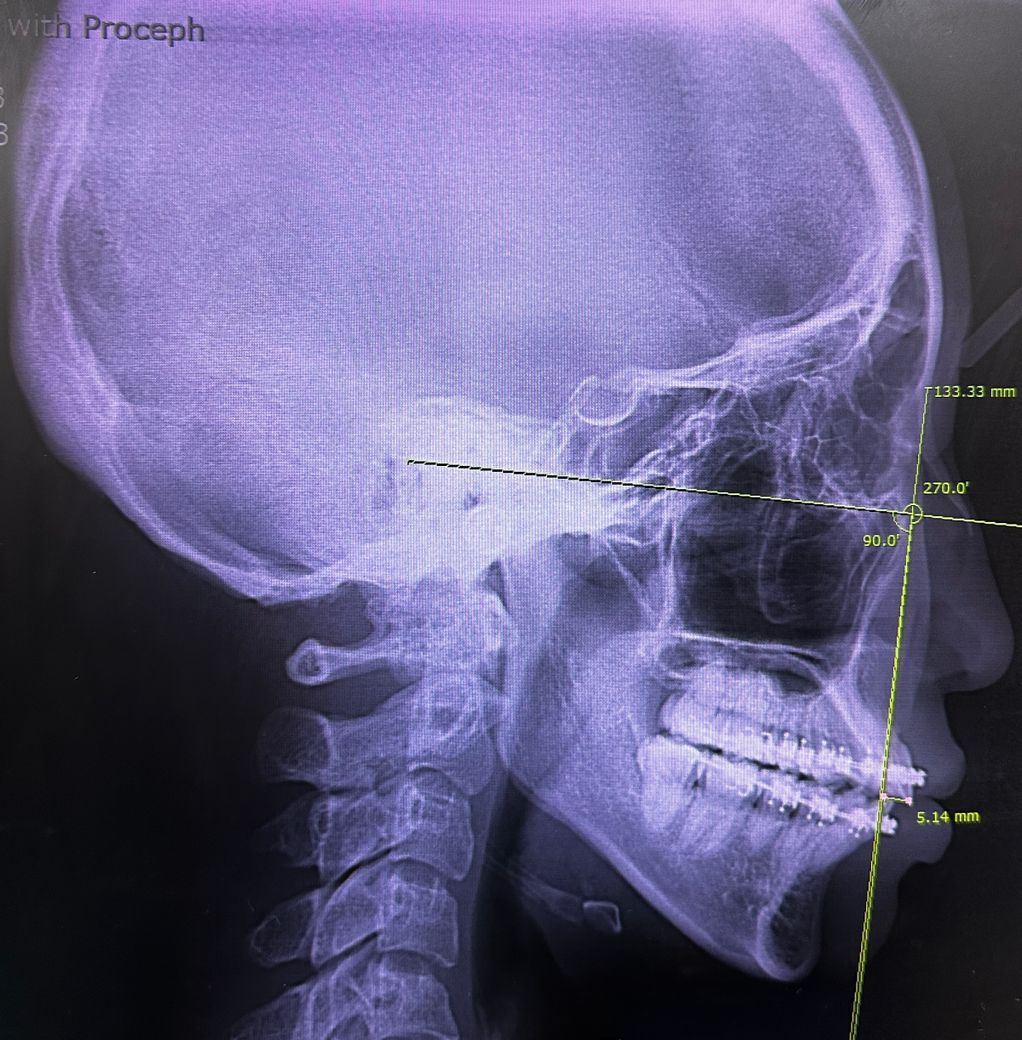

엑스레이 올려드릴테니 상태 한번 봐주실수 있나요!

• 1번 째 사진

교정중 이원교정을 진행중입니다 전 치과에서 비발치로 진행중 교합/뻗침 등 문제로 이원을 하였고 새 치과에선 발치/비발치의 선택을 주셨습니다. 현재 많이 뻗쳐서 새부리 같기도 하고요 뻗침으로 인해 아랫입술이 뒤집어져 정면에서

1. 발치 : 턱 작음, 5번 발치, 앞니를 넣다가 옥니 되지 않도록 어금니 끌어오기, 기도가 좁아 발치 교정 시 숨쉬기 불편해 질 수 있음

2. 비발치 : 상악만 스크류 후방이동, 교합완벽하지 않을 수 있음, 하악 치간삭제(후방 자리 없음), 발치보다 입이 들어가지 않음